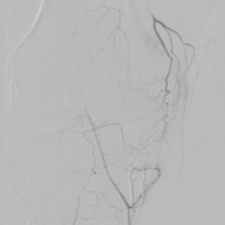

Schultergelenkembolisation

Ein weiteres Einsatzgebiet der Embolisarion/Verödung von kleinen Gefässen sind degenerative Erkrankungen/Verschleiß im Bereich der Schulter. Auch hier kann über einen kleinen Zugang z.B. am Handgelenk oder in der Leiste der Eingriff durchgeführt werden.

Die Eingriffe erfolgen in Kooperation mit dem Orthopädisch-Unfallchirurgisches Zentrum (OUZ).